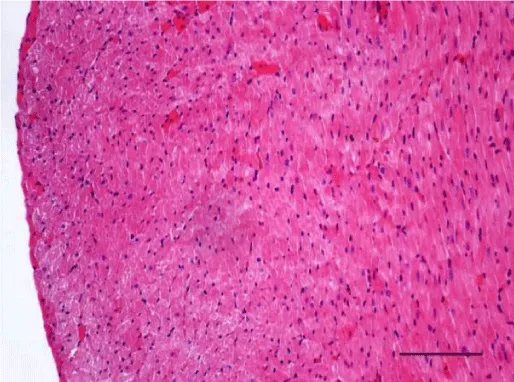

In adult six-month-old rats cardiomyocites from the left and right ventricle appeared eosinophilic on H&E staining, with cross striations and one or two centrally located basophilic nuclei. No striation was noted in the perinuclear zone. Well defined longitudinal and transverse bundles of cardiac muscle cells were seen. Each muscle fiber was enveloped by endomysium built of connective tissue and perimysium containing a capillary network. A certain number of fibroblastic and fibrocytic nuclei were observed among the cardiomyocytes. The presence of capillaries between the muscle cells was also noted. We reported the occurrence of cardiomyocytic hypertrophy and the narrowing of the interstitial space. A mild neutrophil infiltration and pyknotic nuclei were observed, as well as moderately pronounced subendocardial and interstitial fibrosis presenting as eosinophilic fascicles, extending among the cardiac muscle cells. Moderate hyaline degeneration, vacuolization and degradation of the sarcomeres were also noted (Figures 13,14).

In the group of senescent twelve-month-old rats, age-related changes observed in the wall of the left and the right ventricle on H&E staining were best expressed. Bundles of large longitudinally positioned hypertrophic cardiac muscle cells with large basophilic nuclei with reticular structure were seen. We also noted bundles of hypertrophic cardiomyocytes from the transverse layers and further narrowing of the interstitial space. Capillaries in the connective tissue surrounding the muscle fibers were found less often. A well-pronounced neutrophil infiltration and the presence of pyknotic nuclei were observed. Subendocardial and interstitial fibrosis was more manifest and presented as clearly visible eosinophilic fascicles. A major finding was the focal myocytolysis: individual cardiomyocytes which appeared ‘empty’, i.e. no nuclei and cross striations were noted in them, while their cytoplasm stained more intensively eosinophilic (Figures 15,16). When comparing the two ventricles we noted that these changes in myocardial morphology were more extensive and advanced in the wall of the left as opposed to the right ventricle, where hypertrophic and necrotic cardiomyocytes were fewer in number.